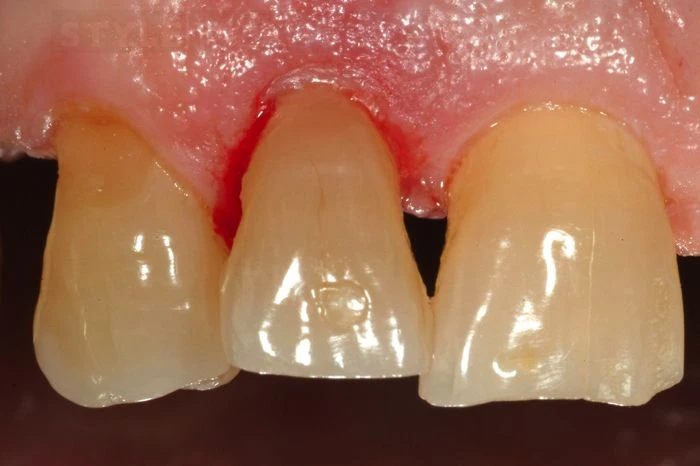

Ngay sau khi bỏ tấm cao su cách ly có thể thấy răng đã được đưa về đúng vị trí. Lúc này chưa cần quan tâm về sự khác biệt màu sắc, nó sẽ được điều chỉnh sau khi răng ngấm nước.

Tiếp theo đánh bóng răng bằng Brownie Shofu và Greenie SHOFU (CA 0404).

Cẩn thận không để thừa chất gắn ở vị trí đường gãy. Nhìn ngoài vị trí đường gãy liên tục rất tốt trong việc loại bỏ chất gắn dư. Có thể thấy rõ sự liên tục là rất hoàn hảo.

Khám sau khi mô mềm lành thương cho thấy lợi phục hồi tốt. Đo túi lợi không thấy bất cứ sự mất bám dính nào ở vị trí kẽ răng. Thẩm mỹ răng hoàn hảo, hài hoà trên cung răng.